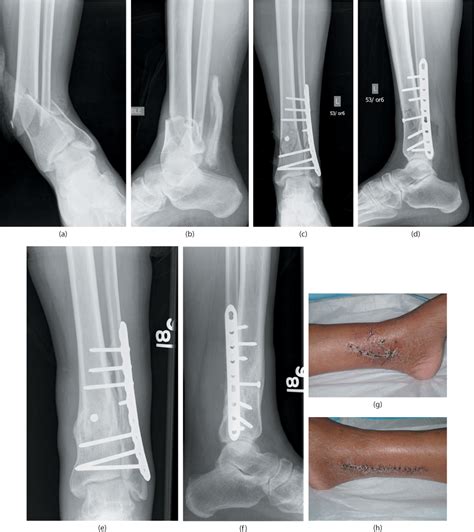

Before we jump into the coding aspects, it’s essential to understand what a distal tibia-fibula fracture actually is. The tibia and fibula are the two long bones in your lower leg. The distal end refers to the part of the bones near your ankle joint. A fracture in this area can range from a hairline crack to a complete break, and it often results from trauma such as falls, sports injuries, or car accidents.

Why is the location so important? Well, fractures in the distal region can be more complex due to the involvement of the ankle joint. These fractures often require surgical intervention to ensure proper alignment and stability. So, when a patient hobbles in with a wonky ankle after a skiing mishap, understanding the nature and location of the fracture is the first step toward accurate diagnosis and treatment.

1. Review the Medical Record Thoroughly: Before you start coding, take the time to review the patient’s medical record carefully. Pay attention to the physician’s notes, X-ray reports, and other relevant documentation.